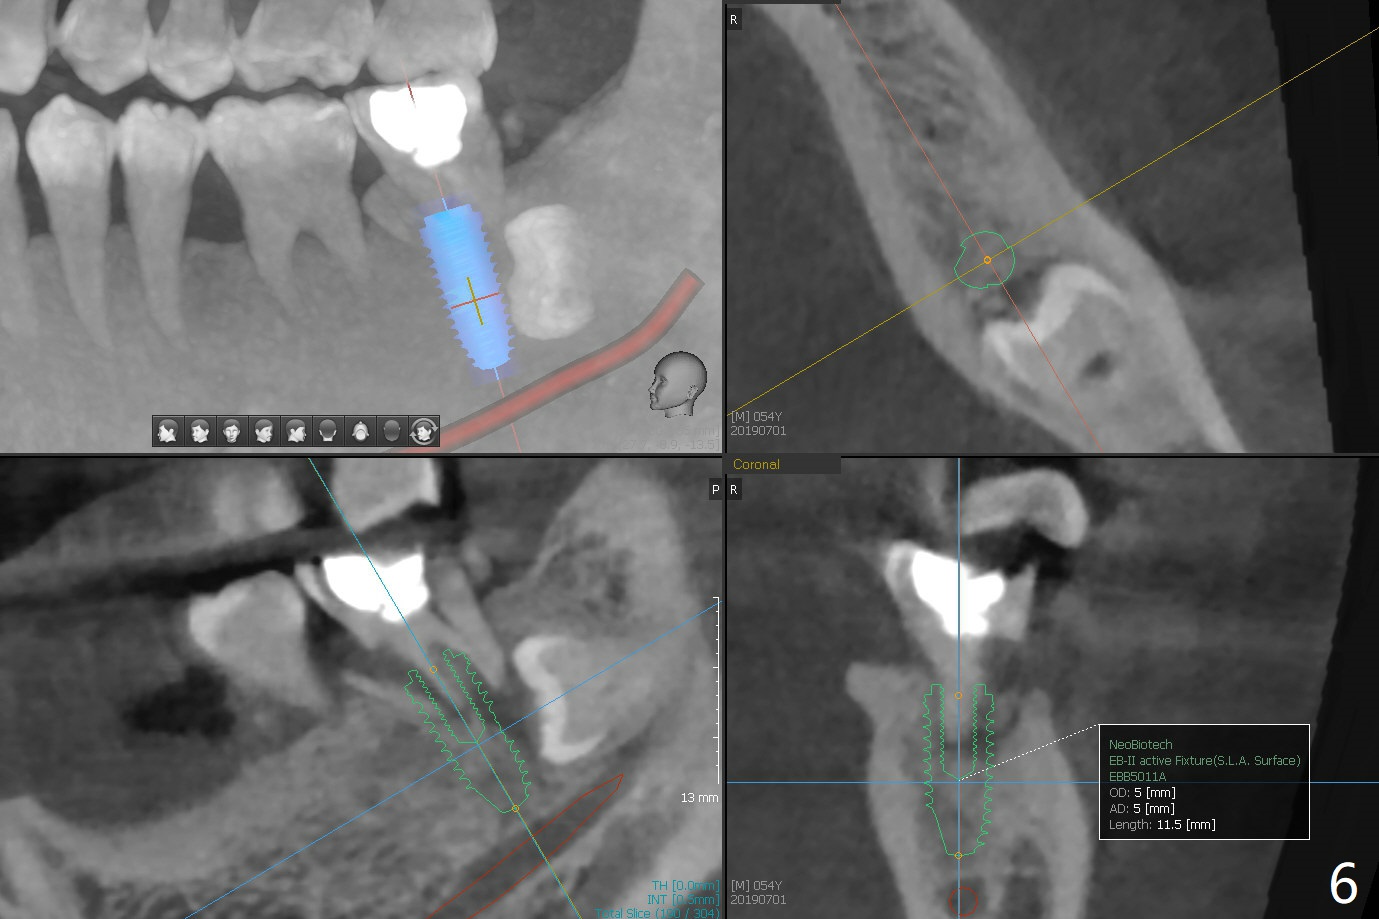

A 54-year-old man returns for #28 and 31 implants 3 months post extraction (#8,9 implants 4 years 5 months post cementation, Fig.1). The buccal plate at #28 is concave (Fig.2 *). After 2.2 mm drill to the depth as lingual as possible (Fig.3 L), use bone expanders through the guide to push the buccal plate out. Use Magic split or bone scalpels and blades to facilitate the expansion if needed. Place mixture of autogenous bone from #18 (Fig.4) and allograft buccally before implant insertion. Vertical fracture of the mesial root at #18 is an incidental finding (Fig.5 M). To avoid the impacted 3rd molar, osteotomy will be initiated as mesial as possible (Fig.6).